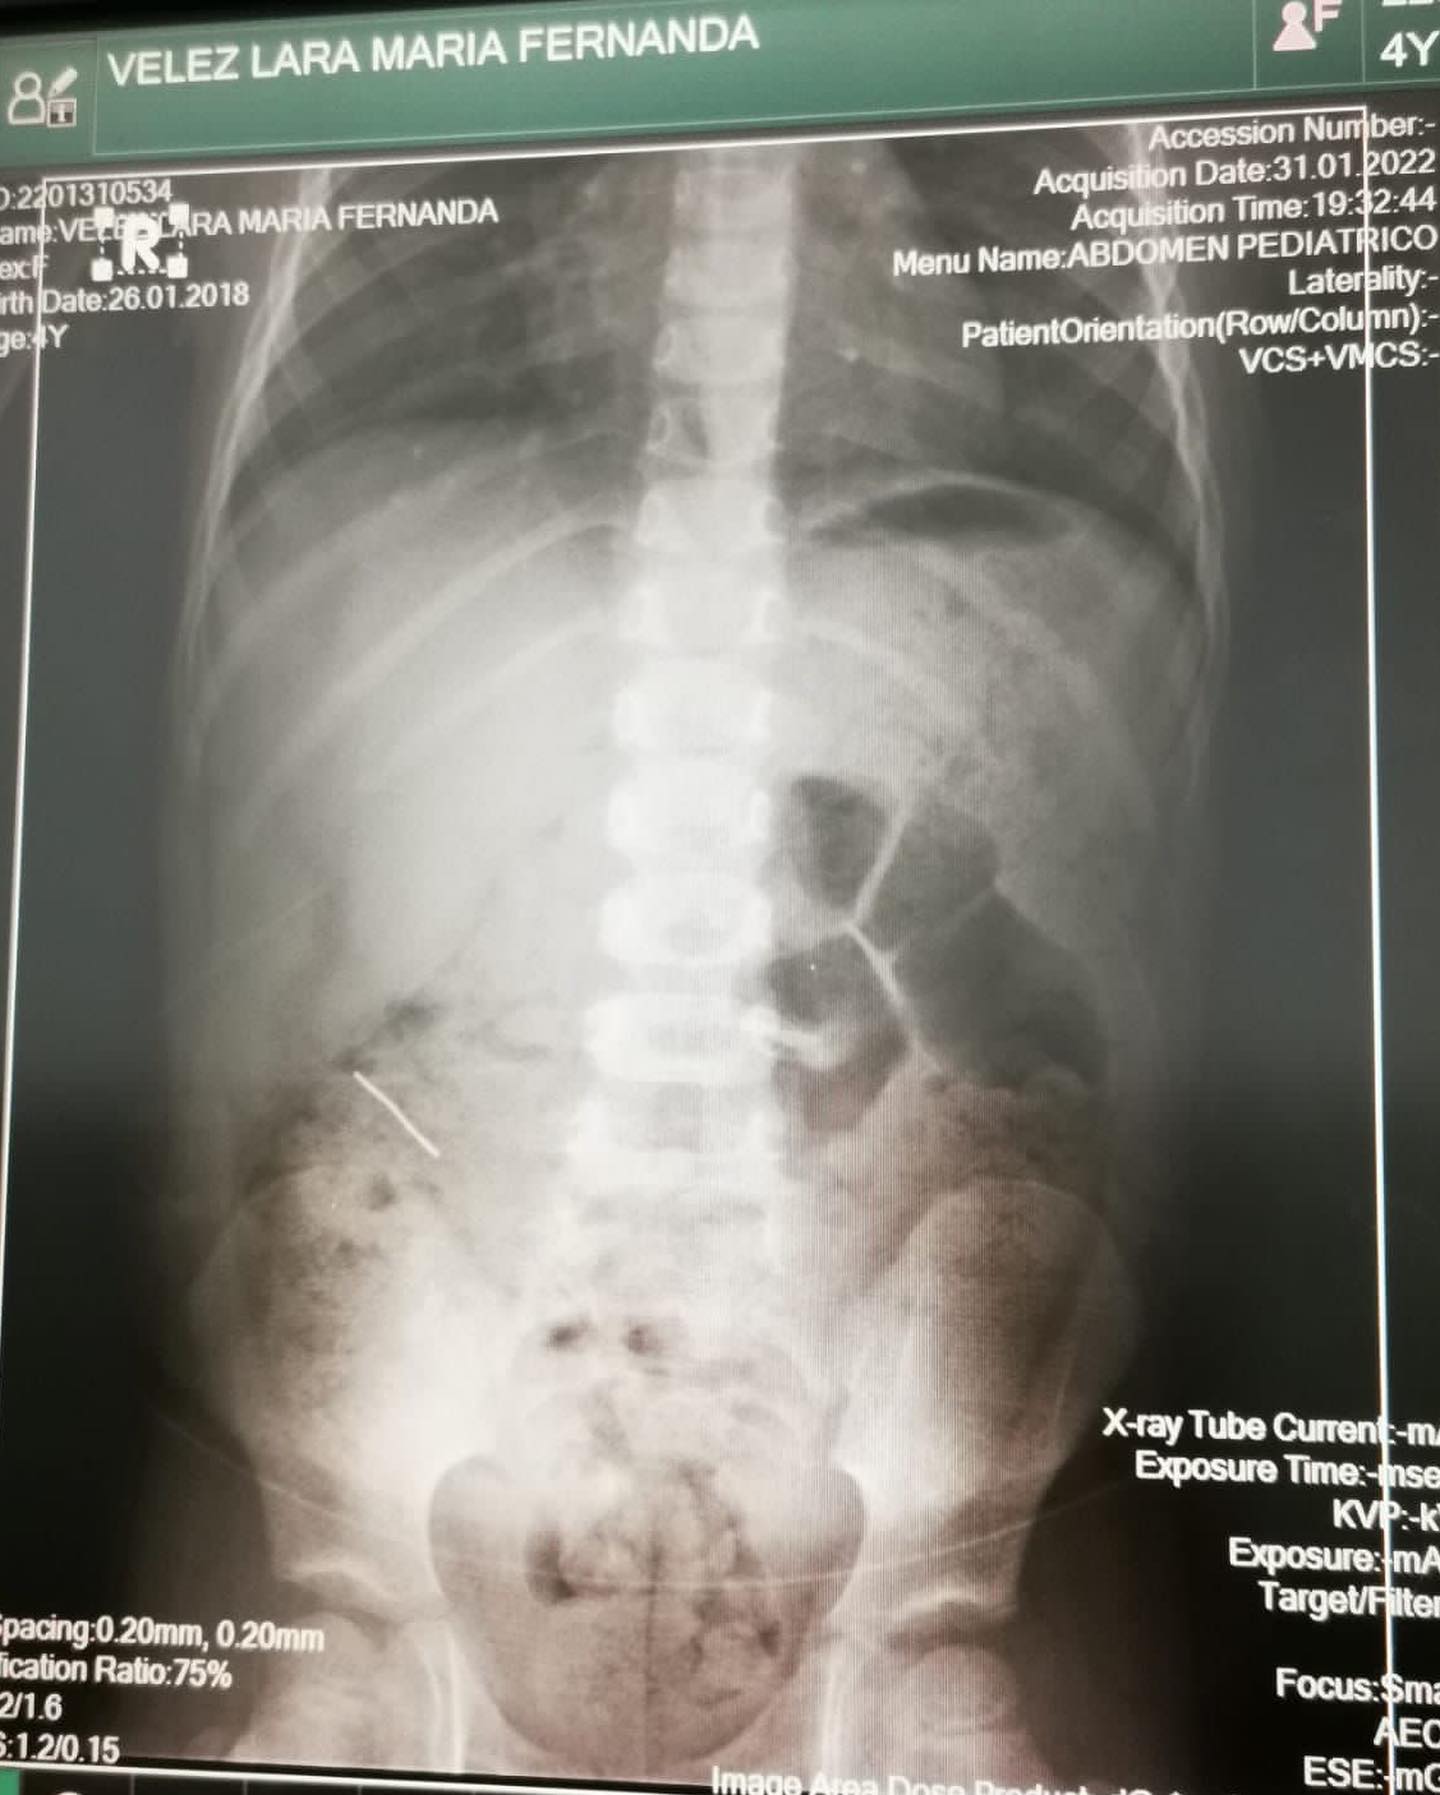

„ Днес дъщерите ми ядаха от тортата, уверени, че всичко в нея е годно за консумация. Изядаха си частите и в този момент имат метал в коремите си. Прилагам фотографията на тортата по какъв начин изглеждаше, когато пристигна и рентгеновите фотоси с метала в стомаха.“